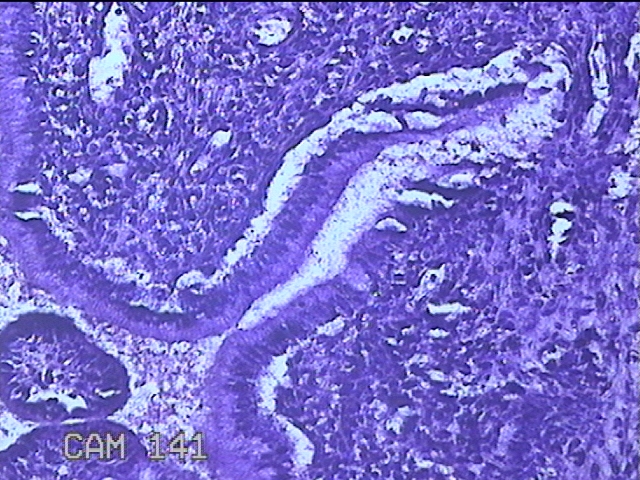

性别

女

年龄

36岁

临床诊断

宫颈赘生物

一般病史

发现宫颈赘生物1个月。

标本名称

大体所见

灰白暗红色肿物1x0.7x0.2cm一个,表面糜烂。

图3